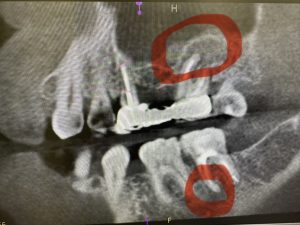

午後最終の方は他院での破折ファイルあり

その先には、病巣が大!

No.6.8.10号を多用しながら、Hファイルも使い、あとUファイル超音波反時計回りでいつの間にか取れていた🤪